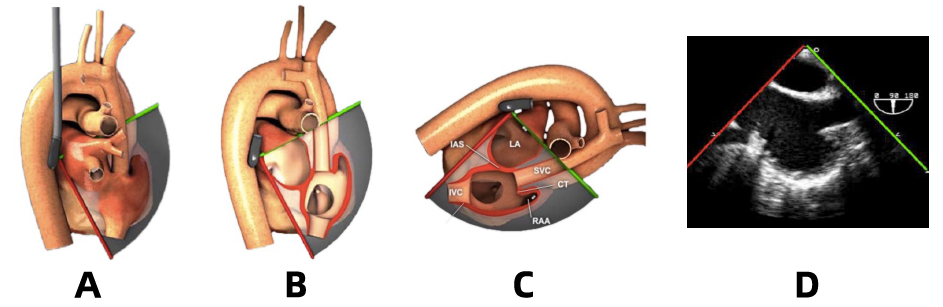

理解超声图像:TEE 探头沿食管内壁前行,晶片直接贴近心脏由后往前扫查获取一扇形切面。可以想象为,沿超声平面「剖开」心脏及大血管结构(图 4),靠近探头晶片的结构呈现于图像的上方(近场)、远离探头晶片的结构呈现于图像的下方(远场)。经过旋转图像转换,最终呈现在屏幕上的图像为相对应的扇形视野。

图 4:TEE 图像示意图(Bicaval view)

A:探头与心脏相对位置;B:「超声刀」剖开结构;C:旋转图像转换;D:真实 TEE 图像